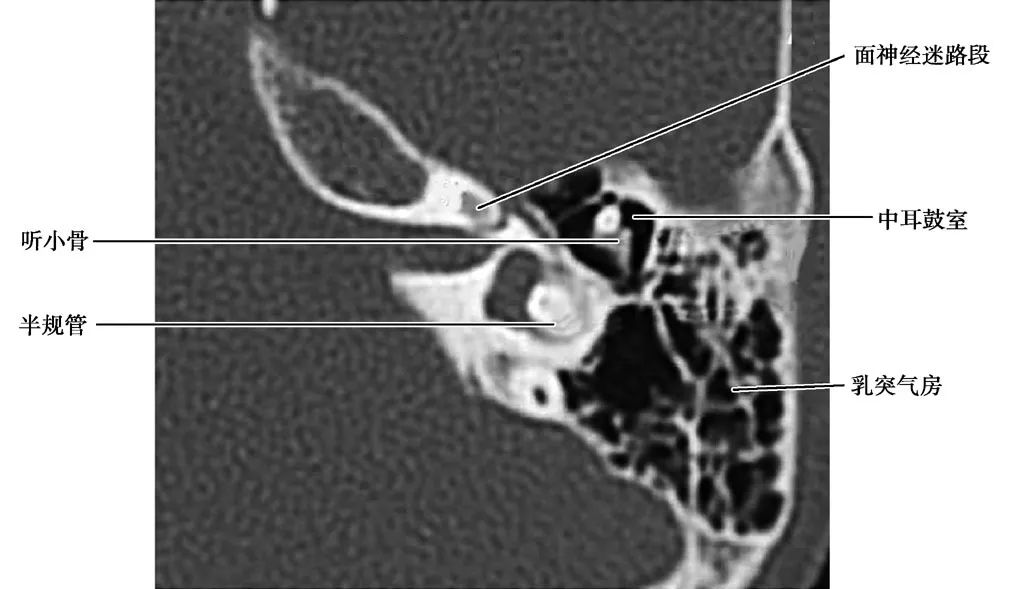

中耳、内耳结构

(CT横断面自上而下)

面神经迷路段

面神经鼓室段

面神经乳突段